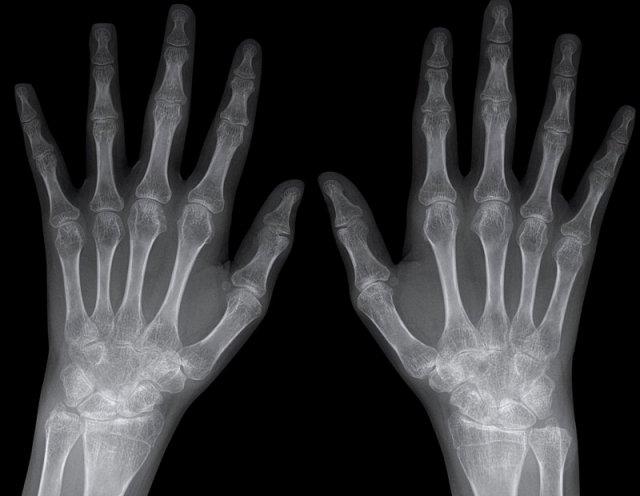

Hình ảnh bào mòn xương vùng rìa điển hình và hẹp khe khớp tại các khớp MCP 3-5.

Lưu ý hình ảnh hẹp khe khớp đồng đều tại các khớp MCP.

Các khớp liên đốt gần (PIP) chỉ biểu hiện hẹp khe khớp tối thiểu.

Đây là trường hợp viêm khớp dạng thấp giai đoạn cuối với các thay đổi bào mòn nặng nề và đứt dây chằng gây trật khớp tại các khớp MCP.

Phân ly xương thuyền – xương nguyệt (mũi tên trắng) là dấu hiệu thường gặp do tình trạng viêm lan tỏa khối xương cổ tay. Cả tình trạng phân ly lẫn viêm đều có thể gây hẹp khe khớp quay – cổ tay.

Lưu ý hình ảnh bào mòn xương đầu dưới xương trụ kèm theo sưng nề phần mềm xung quanh (mũi tên xanh).